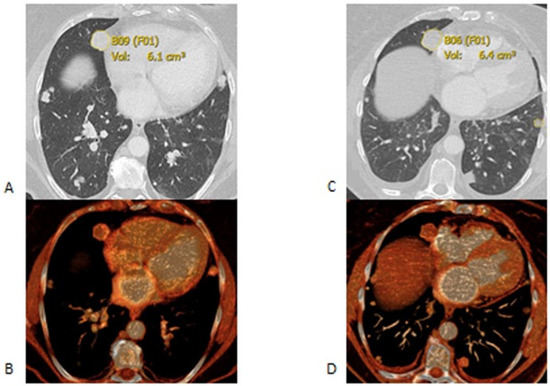

2.2. Imaging Analysis